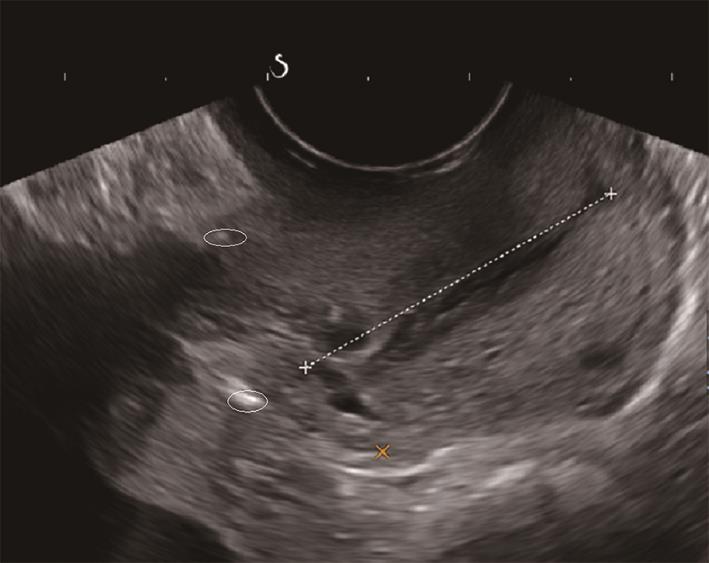

• 剪切波弹性成像测量宫颈硬度的可重复性研究

2023, 48(5):587-590. DOI: 10.13406/j.cnki.cyxb.003223

摘要 (100) HTML (44) PDF 1.18 M (212) 评论 (0) 收藏

摘要:目的 评价剪切波弹性成像(shear wave elastography,SWE)测量育龄期健康未育女性宫颈杨氏模量值的可重复性。方法 由同一名接受过SWE检测培训的高年资医师于同一天不同时间点,前后2次对100名处于育龄期但未育的健康女性宫颈行剪切波弹性成像,测量时选取宫颈4个位点:内口前唇(anterior lip of the inner mouth,IA)、内口后唇(posterior lip of the inner mouth,IP)、外口前唇(anterior lip of the outer mouth,EA)及外口后唇(posterior lip of the outer mouth,EP),获取育龄期健康未育女性宫颈杨氏模量值。使用组内相关系数(interclass correlation coefficient,ICC)评价检查者内可重复性,同时绘制Bland-Altman散点图评价测量一致性。结果 宫颈4个测量位点的前后2次测值均无统计学差异(P>0.05);宫颈IA、EA、EP处杨氏模量值的组内相关系数分别为0.828、0.785、0.768,提示组内可重复性非常好;宫颈IP处杨氏模量值的组内相关系数为0.632,提示组内可重复性好;Bland-Altman散点图提示SWE测量宫颈4个位点杨氏模量值的组内一致性均为好。结论 SWE可用于宫颈硬度的测量,且在宫颈不同位点均具有良好的可重复性与一致性。